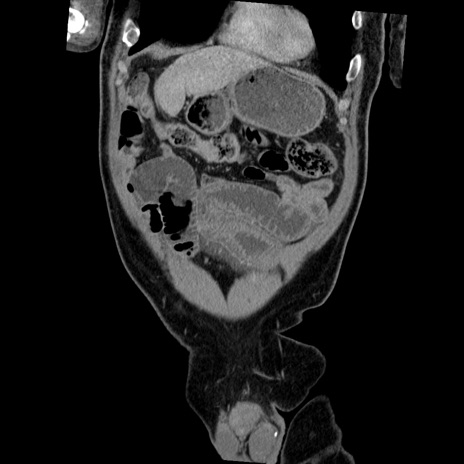

横断像

【症例】50歳代男性

【主訴】腹痛

【現病歴】AVMからの被殻出血のため回復期リハ病棟入院中。 本日午後3時頃急に下腹部痛が出現した。

【既往歴】AVM、被殻出血、虫垂炎、高血圧

【身体所見】意識晴明、左半身不全麻痺、会話の理解は良好、36.5°C、腹部:膨隆、全体に板状硬、下腹部正中に圧痛点あり、反跳痛-、筋性防御不明、右下腹部にope scar

【データ】WBC 9400、CRP 0.06